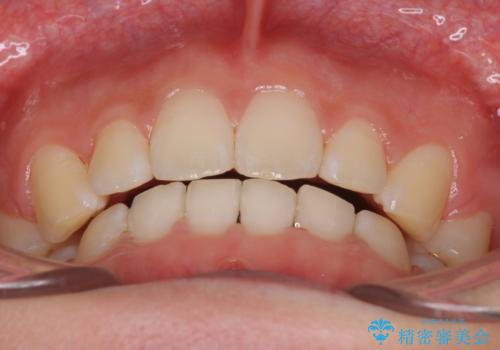

前歯をしっかり下げることで、口元がすっきりしました。

- 横から見たときの口元が出てるの気になるとのことで来院されました。

口元の突出感と口唇の閉じずらさが確認されました。

上下左右の歯を1本ずつ、合計4本抜歯しして前歯を後方に下げて、口元の突出感を改善する計画としました。